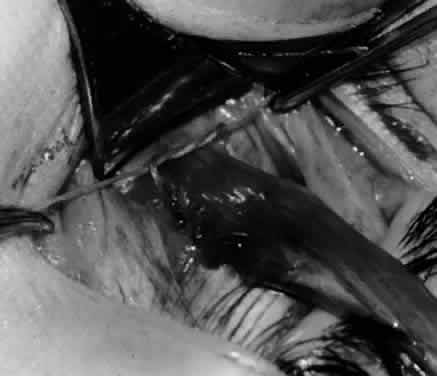

Fig. 26. Cautery is applied to sever the neurovascular bundle, and a sponge is used to protect the sclera and lids from cautery.

Fig. 27. As the neurovascular bundle is severed completely, the inferior oblique muscle will be released of the normal tension provided by the neurovascular bundle on the posterior border of the inferior oblique muscle.

Fig. 28. The inferior oblique muscle is drawn further into the operative field, and a 3-0 Vicryl suture ligature is applied about the belly of the muscle.

Fig. 29. Cautery is used to sever the inferior oblique muscle and to provide hemostasis.